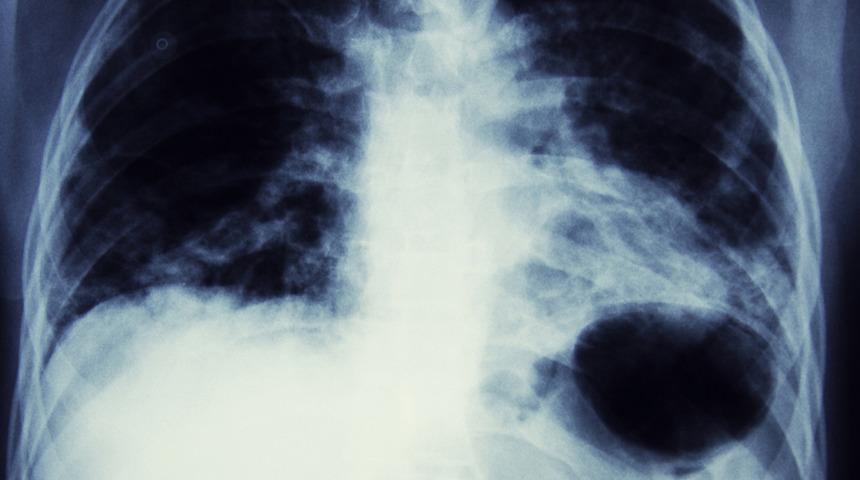

Akciğer kanseri tedavisinde 3 önemli gelişme! Yaşam süresini uzatıyor

Akciğer kanseri özellikle sigara içenler için tehdit oluşturan bir hastalık. Ülkemizde her yıl 40 bini aşkın kişinin akciğer kanseri tanısı aldığına dikkat çeken Prof. Dr. Özlem Er, akciğer kanseri tedavisinde hastalara özel olarak yol çizildiğini söyledi ve yaşam süresini uzatan ve kaliteyi artıran akciğer kanseri tedavisinde yaşanan 3 önemli gelişmeyi anlattı.

Akciğer kanseri dünyada ve ülkemizde kanserden ölümler arasında ilk sırada yer alıyor. Dünyada her yıl 2 milyondan fazla, ülkemizde de 40 bini aşkın kişiye, sigaranın en önemli risk faktörü olduğu ‘akciğer kanseri’ tanısı konuyor. Günümüzde en korkulan kanser türlerinden biri olsa da, tanı ve tedavisinde yaşanan önemli gelişmeler sayesinde hastaların yaşam süreleri uzatılırken, yaşam kaliteleri de artırılıyor. Öyle ki erken tanı konulduğunda; immünoterapi, hedefe yönelik tedavi ile kemoterapi yöntemlerinin kombine edilerek uygulandığı tedavi protokolüyle hastalar uzun yıllar sağlıklı ve aktif yaşamlarına devam edebiliyor.